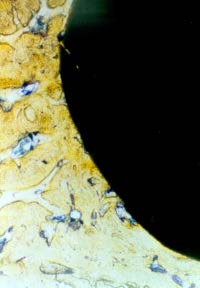

Material and Methodology a) Implant for use in ACIF made of glass-ceramics BAS-O (1996BAS-O ( -1999) ) In 1997 we used an implant made of bioactive glass-ceramics for ACIF in unstable injury to the lower cervical spine as an equivalent replacement of autologous bone drafts (Kokubo 1982,Urban 1992,Yamamuro 1995). It imitated bone tissue properties by its mechanical strength and bioactive properties. In vertical compression glass-ceramics exceeded twice the strength of cortical bone tissue and it was identical in bending strength. Disadvantage of BAS-O glass-ceramics is its fragility causing problems in optimizing the implant shape during biomechanical modelling. Based on mathematical studies we have retained the implant´s shape as a tapered prism with the following dimensions: length 15mm, height 7.8mm ventrally and 6.9mm dorsally, and width 13mm. Strength parameters of this shape exceeded the strength of an autograft (see Figure 1, Figure 2). Implant surfaces that face the vertebral bodies have small indentations of 1mm high. They are intended to secure a firm fixation immediately after the surgery before the fusion due to chemical bond occurs. During the insertion the implant had to be protected from a contact with the metal because of the risk of a damage. We used instruments covered with rubber for handling the implant.